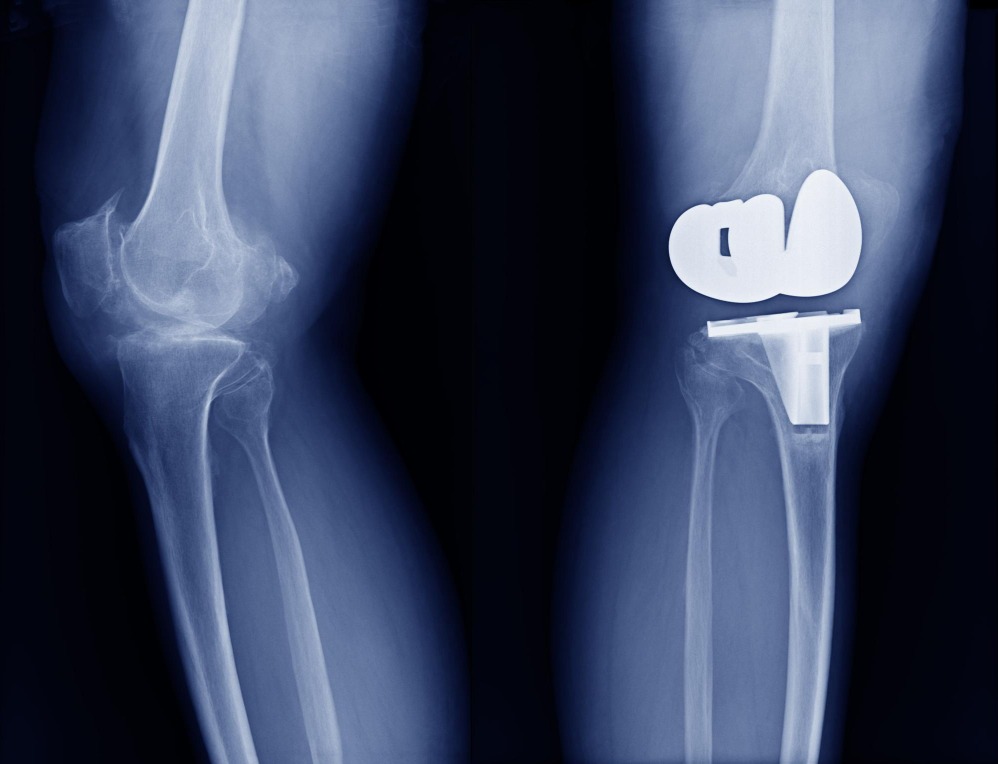

Partial Knee Replacement in Cuff Parade for Targeted Pain Relief

This procedure treats only the damaged portion of the knee, preserving healthy structures for natural movement and shorter recovery time. Patients appreciate how it reduces downtime, supports an active routine and avoids unnecessary intervention on the unaffected areas. The approach feels balanced and practical for those wanting relief without major disruption.